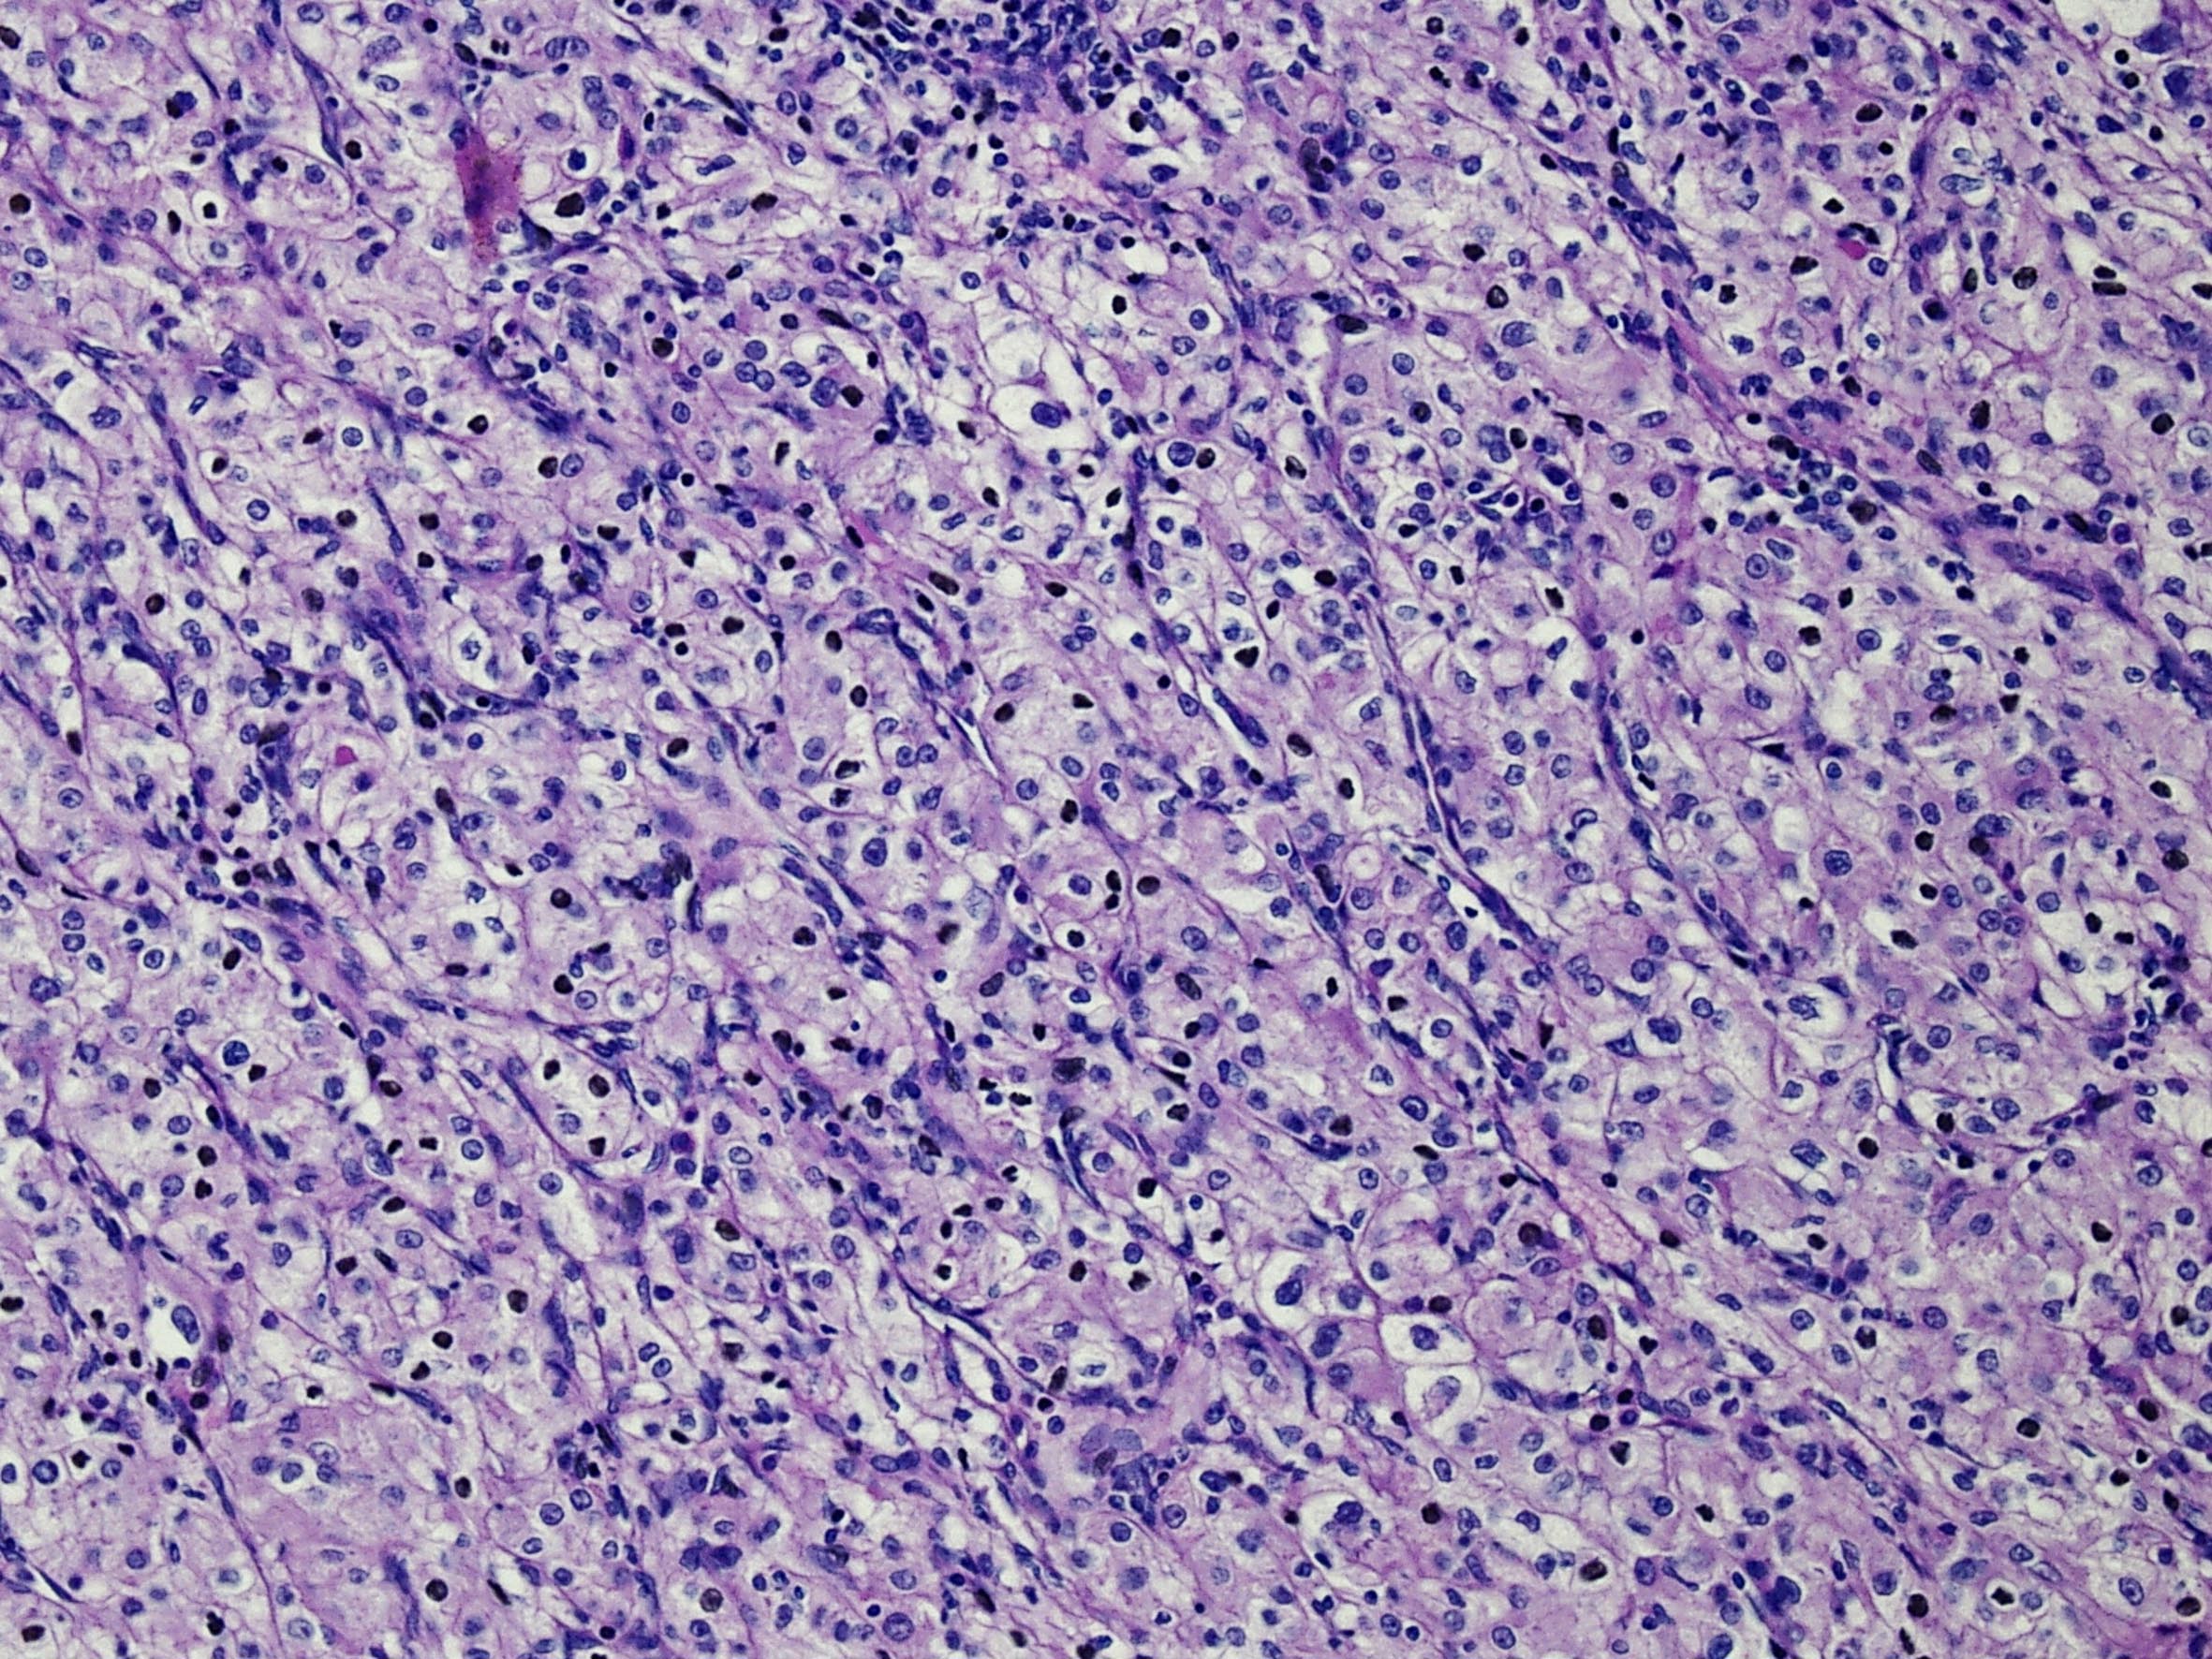

Classification of renal tumors

Case ID: 59